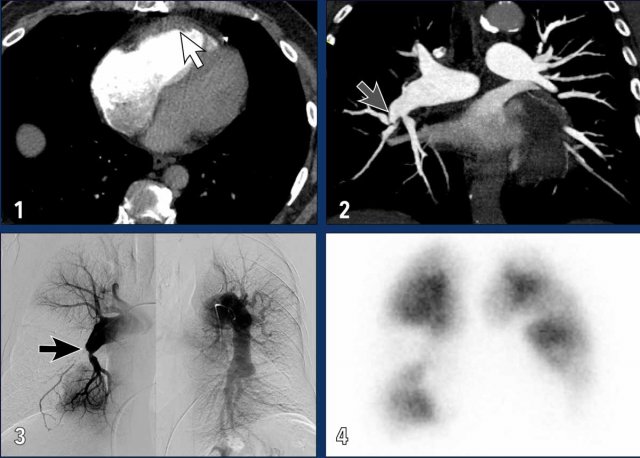

Imaging findings

These images are of a patient with severe CTEPH.

1. Dilatation of RA and RV with muscular hypertrophy of RV (white arrow).

2. Web causing stenosis of this segmental pulmonary artery; one of the features of chronic thromboembolic disease (grey arrow).

3. Pulmonary angiogram showing total occlusion (black arrow) and stenosis of segmental pulmonary arteries, with large perfusion defects.

4. Wedge shaped perfusion defects on a perfusion scan.